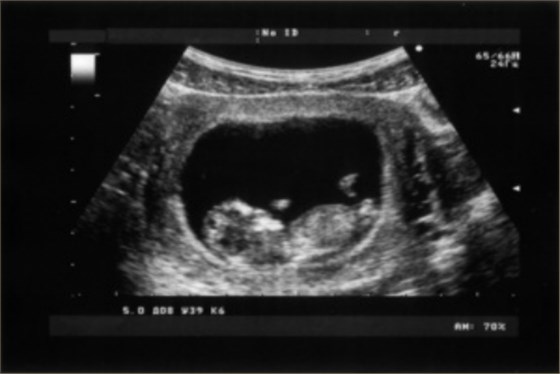

3、應(yīng)用范圍:放射科可以進行全身的多部位的檢查,如頭部、頸部血管、心臟血管、甲狀腺、乳腺、縱隔、腹部臟器等多個部位的檢查,尤其是對占位性病變的檢查具有重要的臨床意義。超聲科可以進行小器官及臟器的檢查,如甲狀腺和乳腺、血管的檢查,心臟和各個瓣膜的檢查,以及肌肉和骨骼的檢查等;